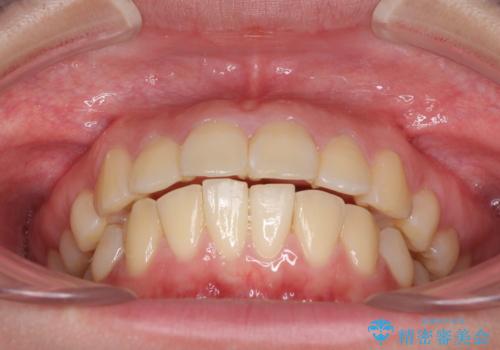

部分矯正で出っ歯になった 出っ歯改善の抜歯矯正

- 上下前歯を部分矯正したところ出っ歯になってしまったとのことで来院された患者様です。

上下左右第一小臼歯4本を抜歯して、積極的に口元を引っ込めるよう、ワイヤー装置にて矯正治療を行うこととしました。

治療後には口が閉じやすくなり、患者様には大変満足していただきました。